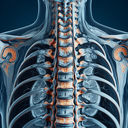

МРТ суглобів

Магнітно-резонансна томографія (МРТ) суглобів є цінним діагностичним інструментом, який дозволяє лікарям отримати детальну оцінку структур суглобів, включаючи кістки, хрящі, зв'язки, сухожилля та м'які тканини. Основні показання для проведення МРТ суглобів включають: 1. **Болі у суглобах**: Якщо у пацієнта є хронічні або гострі болі, які не піддаються звичайному лікуванню і діагностика іншими методами не дала результату...